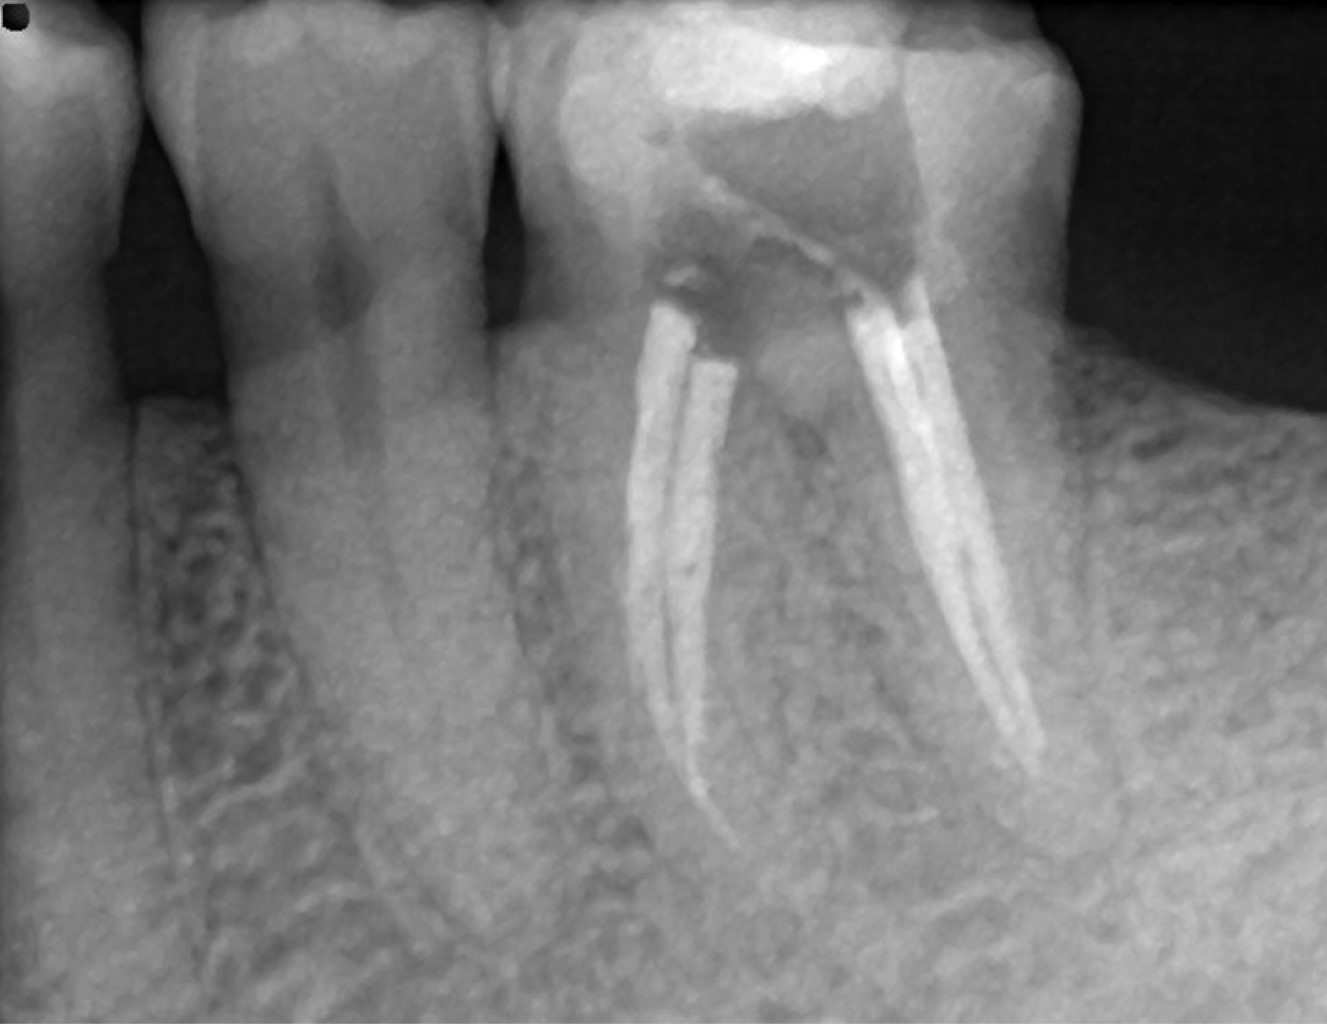

Figure 1

Figure 2

Figure 3

Figure 4